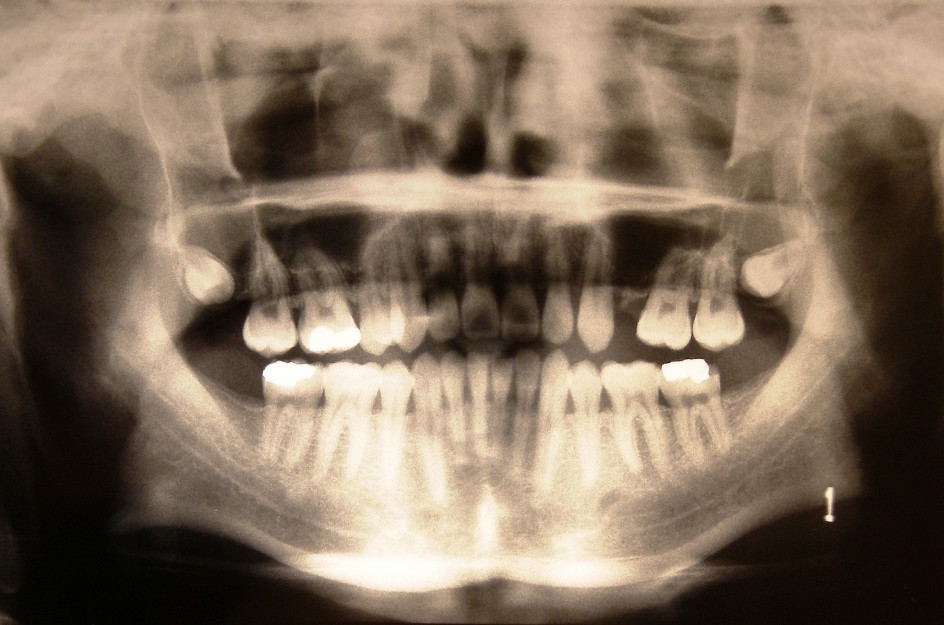

В «стране победившего социализма» люди питались достаточно плохо — хороший белок был дефицитом, в продаже было мало фруктов и овощей (особенно зимой), из-за чего у многих граждан уже к 30-40 годам были плохие зубы. Плюс в СССР не существовало нормальной стоматологии — дырявые зубы сверлили «пыточной» бормашиной на низких оборотах, без наркоза, после чего залепляли серым и шершавым цементом (с отвердителем, от которого за 5 метров несло ацетоновой вонью) — из-за чего люди в СССР очень не любили ходить к зубным врачам.

В «стране победившего социализма» люди питались достаточно плохо — хороший белок был дефицитом, в продаже было мало фруктов и овощей (особенно зимой), из-за чего у многих граждан уже к 30-40 годам были плохие зубы. Плюс в СССР не существовало нормальной стоматологии — дырявые зубы сверлили «пыточной» бормашиной на низких оборотах, без наркоза, после чего залепляли серым и шершавым цементом (с отвердителем, от которого за 5 метров несло ацетоновой вонью) — из-за чего люди в СССР очень не любили ходить к зубным врачам.

Как итог — мало у кого в СССР были хорошие зубы и белоснежная улыбка. Многие ещё и сейчас по старой привычке продолжают бояться походов к зубным врачам и стыдливо прячут зубы, улыбаясь в стиле «куриная попка». Запомните, друзья — сейчас нет нерешаемых проблем с зубами, и к тому же всё сейчас делается совершенно безболезненно. Так что зубных врачей бояться не нужно)